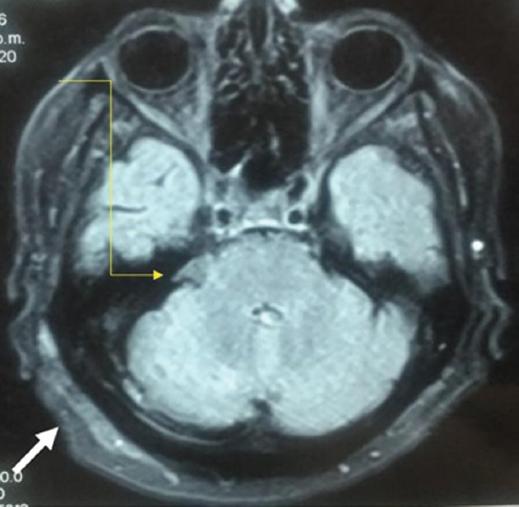

Abordaje microquirúrgico con hallazgos de compresión por la arteria basilar y la vena petrosa superior, en la que se coloca, posterior a la disección aracnoidea, el implante de quitosana para separar el nervio trigémino. Sin complicaciones transoperatorias. Descenso gradual de oxcarbazepina y retiro total a 3 meses del posoperatorio. Tras 7 años de seguimiento, sin reincidencia del dolor neuropático y sin tratamiento farmacológico (Figura 1 y Tabla 1).

Figura 1 Resonancia magnética axial simple en T1 con evidencia del implante-esponja en la cisterna trigeminal a las 48 h de posoperatorio (flecha amarilla). Se observa un segundo implante de quitosana en una conformación en bicapa en la zona dural de la craniectomía (flecha blanca).